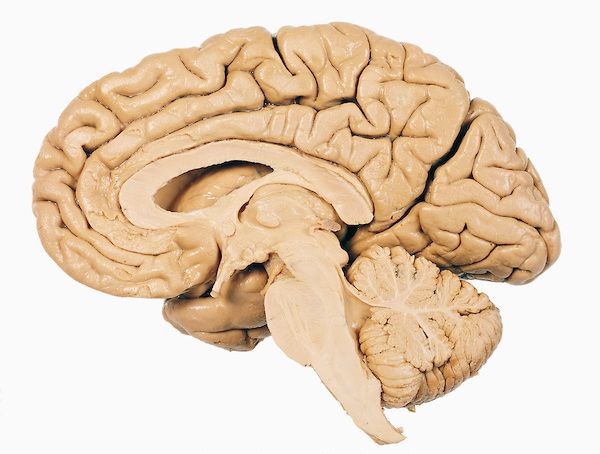

我们先通过一个脑半球切片来看一下大脑的几个主要部分:

我们把大脑从头部取出,然后移除左半球,然后我们就能好好看看内部了。

神经科学家Paul MacLean做了一个简单的图,来阐述我们前面提到的爬虫类脑最早出现——然后是哺乳动物对脑进行了完善——最后又进行了完善后成为了我们现在的大脑三元件的理论。

这就是我们的脑的大概分布:

我们分部分来看 :

接下来,我们退出去,再看一下脑的横切面,这次不是从前往后切,而是从中间切。

大脑的材料可以分为灰质和白质。灰质看上去颜色更深,由神经元的细胞组成,白质则主要由链接轴突组成。白质之所以是白色是因为这些轴突通常被髓鞘包裹着。

灰质主要有两个部分——边缘系统的内部和脑干,以及皮质外层硬币那么厚的部分。剩下来的大块的白质主要就是皮质神经元的轴突组成的了。皮质就像一个指挥中心,把很多命令通过白质中的轴突传播下去。